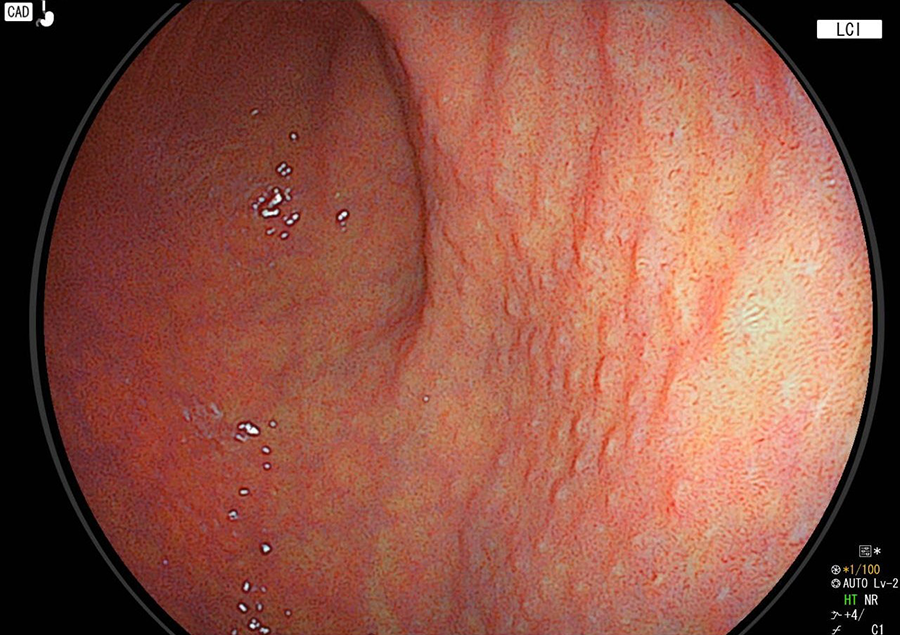

正常の胃

正常の胃粘膜は光沢がありすべすべです。